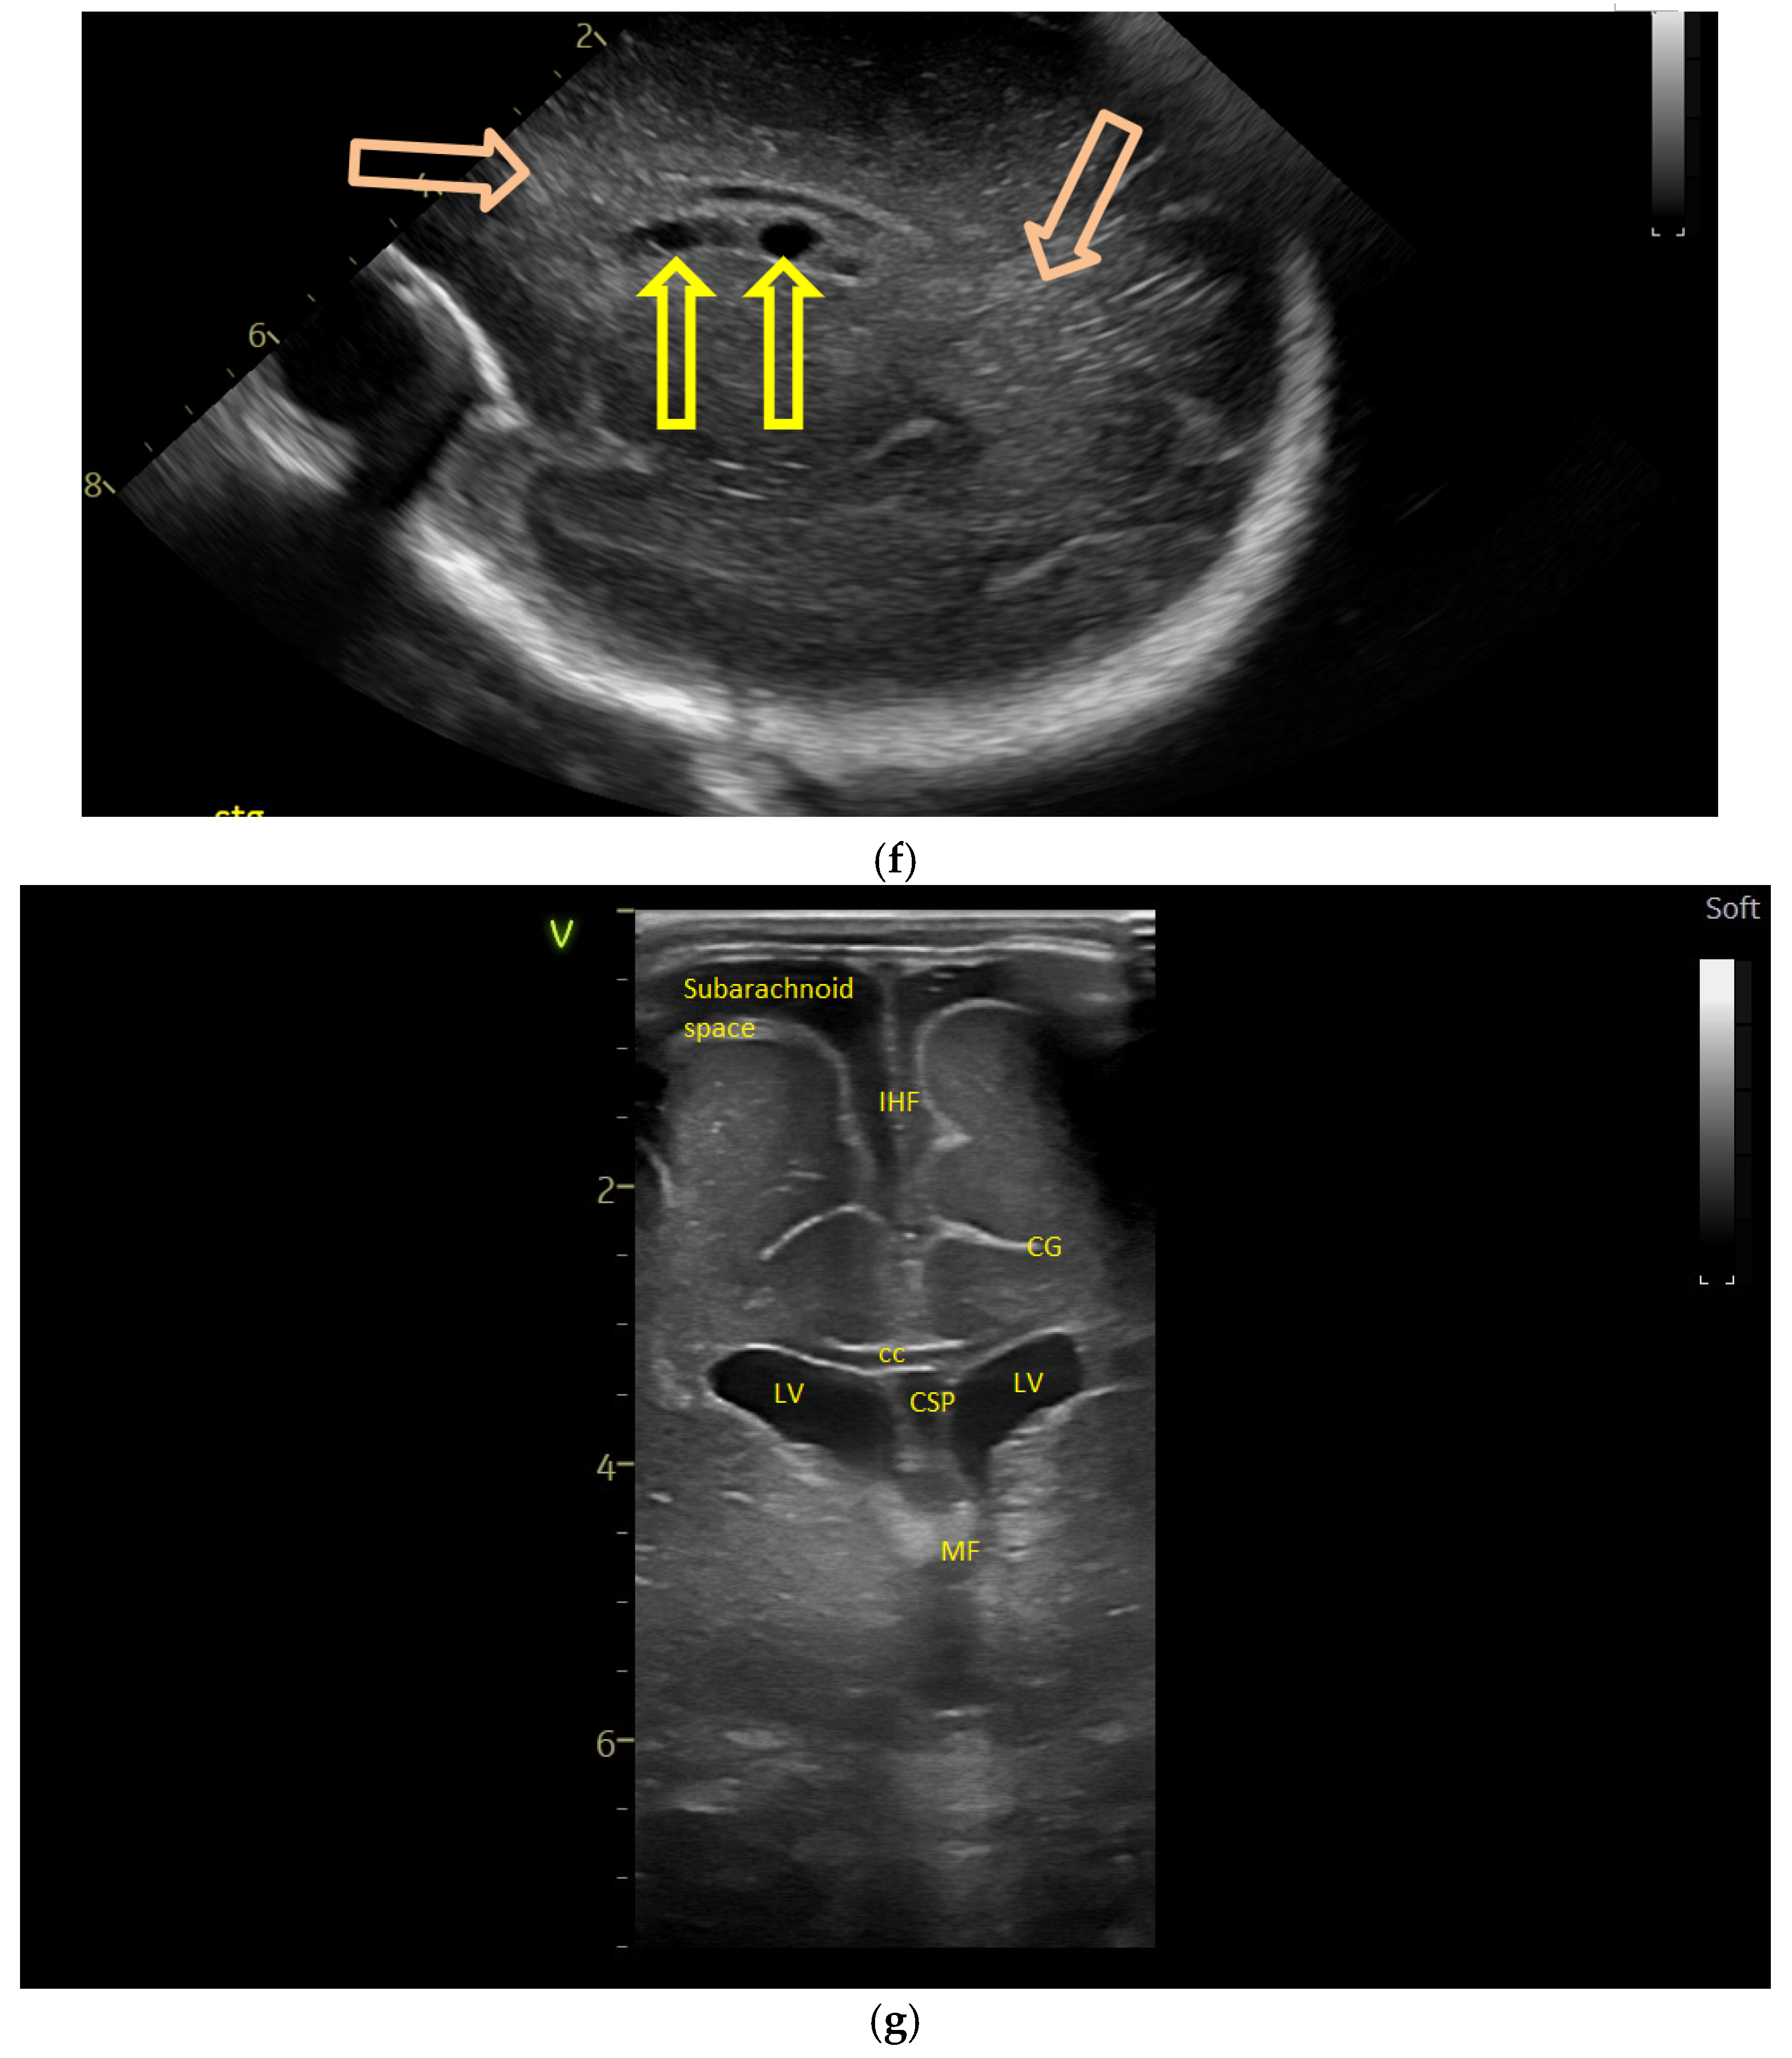

(a) Cranial ultrasound. Day one. Coronal view. D1 and D2—Levine index measurement. D3—cisterna magna measurement (personal image collection). (b) Cranial ultrasound. Day one. Coronal view. Lateral ventricle dilatation. LV—lateral ventricles. PC—plexus choroidus (personal image collection). (c) Cranial ultrasound. Day one. Right lateral ventricle. D1—thalamo-occipital distance measurement. Yellow arrow—parieto-occipital hyperechoic images (personal image collection). (d) Cranial ultrasound. Day one. Left lateral ventricle. D1—thalamo-occipital distance measurement. Yellow arrow—parieto-occipital hyperechoic images (personal image collection). (e) Day three. Cranial ultrasound. Coronal view. Ventricular asymmetry. D1 and D2—Levine index measurement. D3 and D4—anterior horn width measurement. Left ventricular enlargement (personal image collection). (f) Day three. Cranial ultrasound. Coronal view. Ventricular asymmetry (left ventricle larger than right ventricle). Yellow arrows—periventricular hyperechoic images are becoming more visible (personal image collection). (g) Day three. Cranial ultrasound. Coronal view. Linear probe. Ventricular asymmetry (left ventricle larger than right ventricle). LV—lateral ventricle (anterior horns). IHF—interhemispheric fissure. Yellow arrows—hyperechoic images in the thalamic-caudate groove (suggestive of a germinal matrix hemorrhage) (personal image collection). (h,i) Day 13. First LP. Cranial ultrasound. Coronal view. Up (before LP). D1 and D2—Levine index measurement. LV—lateral ventricles (anterior horns). IHF—interhemispheric fissure. Down (after LP). Dimensions of ventricles were reduced after LP. D1 and D2—anterior horn width. LV—lateral ventricles (anterior horns). OH—occipital horn (personal image collection). (j,k) Day 19. Second LP. Cranial ultrasound. Coronal view. Dimensions of ventricles were reduced after LP. Left (before LP). D1 and D2—Levine index measurement. Right (after LP). D1 and D2—Levine index measurement (personal image collection). (l) Day 39. Cranial ultrasound. Coronal view. Yellow arrows—periventricular cystic hyperechoic images—suggesting periventricular leukomalacia (cystic form) (personal image collection). (m) Head circumference-for-age. “X” symbols represent the measurements performed from birth and follow-up examinations. Initially, the head circumference was under the curve (personal image collection) [28].

After 72 h, the patient was extubated. The CUS showed bilateral IVH (grade III Volpe/Papile) (Figure 1e,f).

During the in-stay, two lumbar punctures (LP) were performed (Figure 1h–k).

In evolution, our patient presented bilateral ventricular dilatation and bilateral PVL (cystic form, grade III) (Figure 1l). The neurological assessment established eye contact and the infant could hold its head during the traction maneuver. The passive tone assessment showed the “scarf sign”, with the elbow at the midline bilaterally and a popliteal angle of 90°. The deep tendon reflexes (DTRs) were symmetrical.